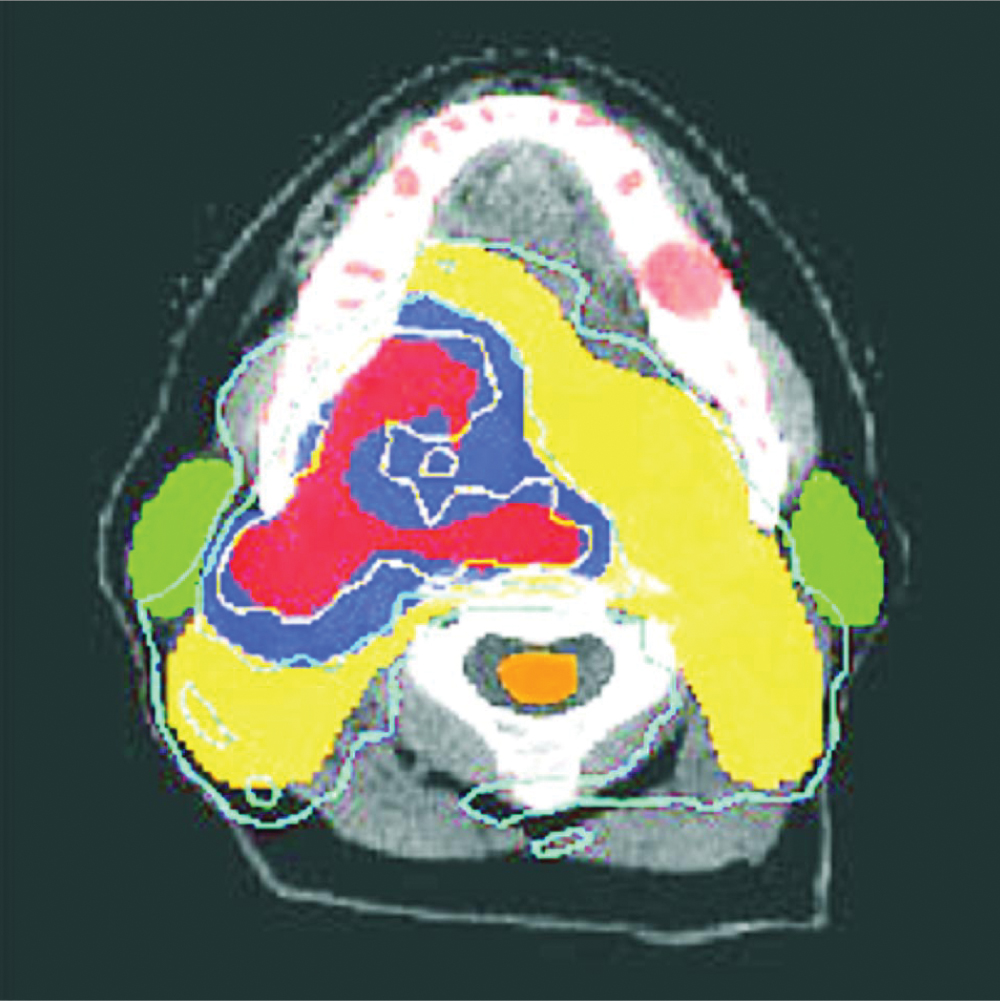

Figure 6 provides another example of IMRT treatment. 14 In this case, the tumor has originated in the base of the tongue. Such tumors spread along the cervical lymph-node chains that run down along each side of the neck. The parotid glands on either side of the jaw are susceptible to radiation damage, which results in reduced production of saliva. Besides being extremely uncomfortable, xerostoma, or dry mouth, can make it difficult for the patient to maintain the diet needed during therapy and can result in long-term damage to gums and teeth. Exceeding the tolerance of the spinal cord can lead to nerve damage or even permanent transection of the spinal cord in the neck, causing paralysis or death. An IMRT treatment that spares these structures allows the delivery of sufficiently high doses to the target volume to improve the chances of controlling the tumor.

IMRT treatment in the head for a tumor at the base of the tongue and right tonsil. This CT reconstruction plane shows the base of the head from below; the white arc is the lower jaw. The colored regions are cross sections through the planned treatment target volumes, identified from positron emission tomography (PET) and contrast-enhanced CT. In the red region, the PET scan showed high oxygen deficiencies, which indicates tumor cells. The 80-gray isodose line (1 Gy = 1 J/kg) surrounding this region shows that the region received a dose of 80 Gy or higher. The contrast-enhanced CT scan indicated possible growth of tumor cells into the blue region. The IMRT delivered 70 Gy to this region. The yellow target was formed to account for known patterns of spread into lymph nodes; that area received a dose of 50 Gy. The parotid glands (green) were spared the higher doses and will continue to function to produce saliva. The spinal cord (orange) was shielded to receive lower that 35 Gy, safely below the dose that can cause neural damage.

(Courtesy of Clifford Chao, University of Texas Cancer Center.)